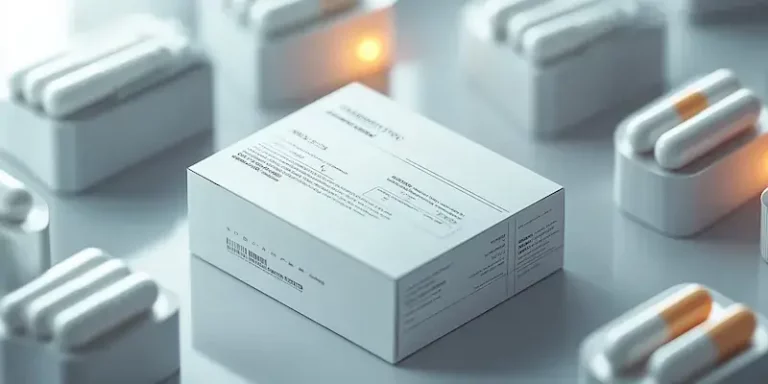

Opakowania na leki odgrywają kluczową rolę w zapewnieniu bezpieczeństwa i skuteczności farmaceutyków. Na rynku dostępnych jest wiele rodzajów opakowań, które…

Papierowe opakowania na leki zyskują coraz większą popularność w branży farmaceutycznej, a ich zalety są liczne i różnorodne. Przede wszystkim,…

E-recepta, znana również jako recepta elektroniczna, to innowacyjne rozwiązanie, które zrewolucjonizowało sposób wystawiania i realizacji recept w Polsce. Jest to…